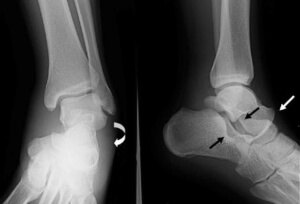

Лечить растяжение можно после рентгена поврежденной ноги.

Для удобства диагностирования и выбора методов лечения травмы поделены на группы. Критерии — степень повреждения тканей и клинические проявления. Разрыв связочного аппарата классифицируется:

1 степень. Незначительный надрыв отдельных волокон или сформированных из них пучков. Поврежденный голеностопный сустав хорошо прощупывается через кожу, объем движений нарушен слабо или полностью сохранен. Пациент способен непродолжительное время опираться на стопу, не ощущая выраженной боли.

2 степень. Диагностируется надрыв большого количества соединительнотканных волокон. При пальпации пострадавший жалуется на болезненность, а сам сустав почти не прощупывается из-за нарастающей отечности. Симптоматика выражена значительно сильнее. Все попытки пострадавшего опереться на поврежденную ногу вызывают сильнейшую боль, сходную с возникающей при вывихах или переломах.

3 степень. При таком повреждении происходит полный отрыв одной, а иногда и нескольких связок от костного основания. Ощущения после разрыва связок голеностопа напоминают признаки перелома костей. Быстро формируется обширный отек и гематома. Функциональная активность стопы снижена настолько, что упор на нее невозможен по нескольким причинам. Во-первых, это сильнейшая боль. Она настолько интенсивна, что пострадавший может потерять сознание. Во-вторых, серьезно нарушено анатомическое соотношение суставных элементов.

Независимо от выраженности симптоматики больному показана дифференциальная диагностика. Ее результаты помогут наиболее информативно оценить степень повреждения и количество развившихся осложнений.